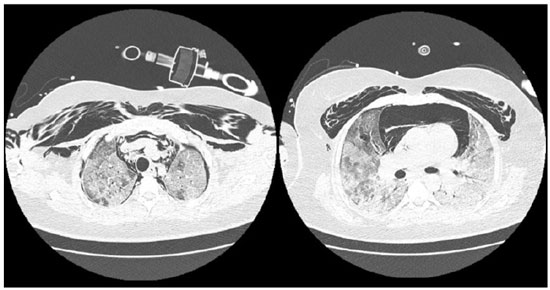

Após o início de VM invasiva, apresentou assincronias frequentes, dificuldade de manter parâmetros VM protetora, com necessidade de ajustes frequentes no ventilador e de associar sedativos em altas doses e bloqueador neuromuscular (fez uso de midazolam, propofol, fentanil e pancurônio). Exame de imagem após intubação orotraqueal, mostrava cânula endotraqueal bem-posicionada, opacidades parenquimatosas difusas, cateter venoso central à direita e sem sinais de pneumotórax (vide figura A). Entretanto, no dia 05/04/21 paciente apresentou ao exame físico enfisema subcutâneo extenso em região torácica e cervical, realizou exames de imagem que evidenciaram extenso enfisema subcutâneo e moderado pneumomediastino (vide figuras B e C). Discutido caso com equipe de cirurgia torácica que optou por manter tratamento conservador e não realizar procedimentos invasivos, como drenagem de subcutâneo.